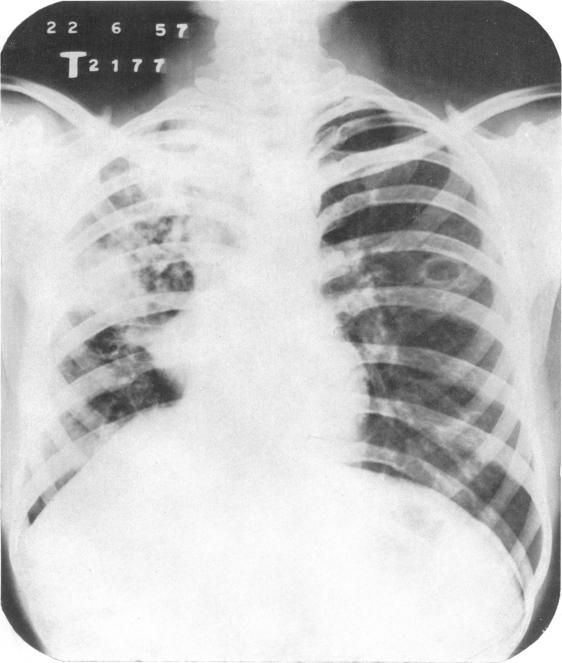

In India, as in most under-development countries, the tuberculosis problem is aggravated by an acute shortage of sanatorium beds. The number of active cases of tuberculosis in the country has been estimated at 2 (1/2) million, but only 23 000 tuberculosis beds are available. In these circumstances great importance attaches to the possibility of applying mass domiciliary chemotherapy as a substitute for sanatorium treatment in cases of pulmonary tuberculosis. The findings of the present study, based on a comparison of the two types of treatment over a period of 12 months, show that despite the manifest advantages of sanatorium care-rest, adequate diet, nursing and supervised medicine-taking-the merits of domiciliary chemotherapy are comparable to those of sanatorium treatment, and that it would therefore be appropriate to treat the majority of patients at home, provided an adequate service were established.